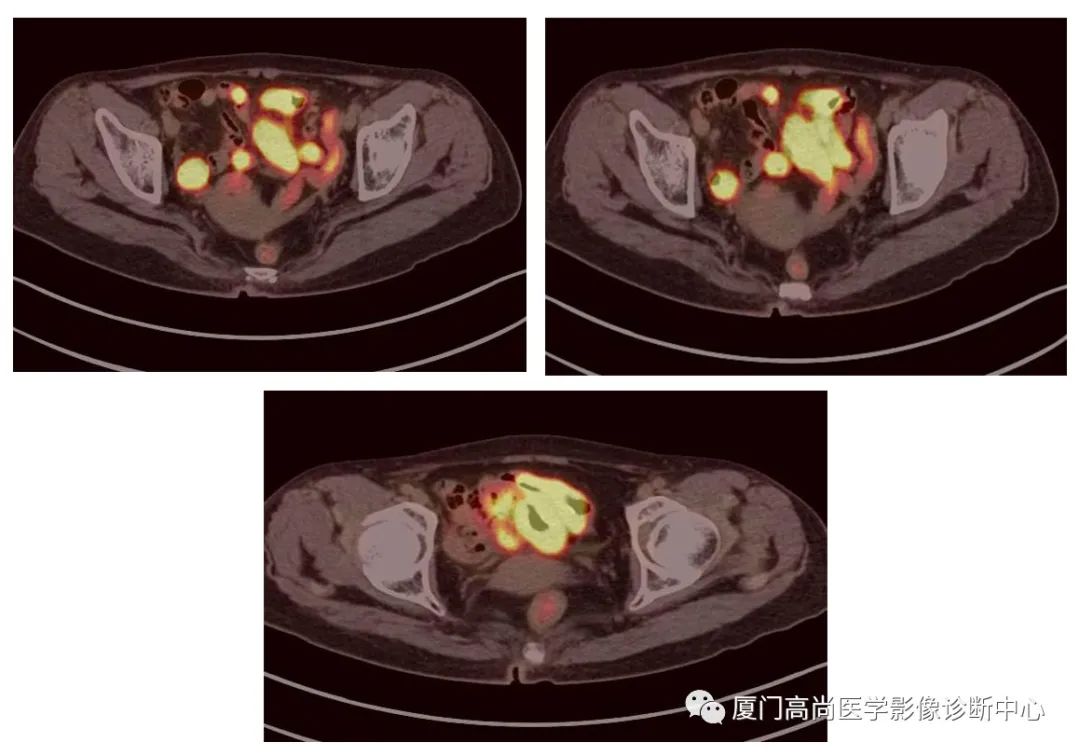

腹腔淋巴結(jié)腫大

PET/CT發(fā)現(xiàn) :左心房、右心房見團(tuán)塊狀FDG攝取增高;雙側(cè)腎上腺增大,F(xiàn)DG攝取增高;膽囊和胃壁結(jié)節(jié)樣FDG攝取增高;小腸多節(jié)段腸壁增厚,F(xiàn)DG攝取增高;腹膜后、腹腔及盆腔多發(fā)淋巴結(jié)腫大,F(xiàn)DG攝取增高;上述考慮為淋巴瘤

經(jīng)腎上腺穿刺活檢 :病理證實(shí)為彌漫大B細(xì)胞淋巴瘤